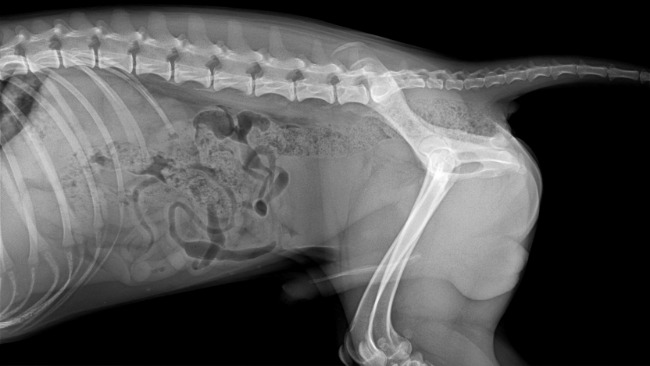

Stefan to kundelek z domieszką beagla. Został adoptowany przez nas rok temu z Krakowskiego schroniska jako szczeniak. To była nasza najlepsza decyzja. Wnosi do naszej rodziny wiele szczęścia. Jest jak nasze 3 dziecko. Kocha ludzi, kocha życie. Jednak mimo młodego wieku już dużo przeszedł. Już w 6 miesiącu swojego życia zaczęła się jego choroba. Stefek z energicznego psiaka w sekundzie stał się apatyczny, miał gorączkę, nie jadł, nie pił, nie wstawał, trząsł się z bólu. Pierwsza diagnoza była powiązana z zapaleniem pęcherza, jednak nie trafna. Niedługo później ataki powróciły. Po wykonaniu mnóstwa badań stwierdzono u niego najprawdopodobniej SRMA steroidozależne zapalenie opon mózgowo-rdzeniowych. Jednak żeby mieć pewność potrzeba jest dalsza diagnostyka w tym tomografia komputerowa i pobranie płynu mózgowo-rdzeniowego. Są to bardzo kosztowne badania, bez których się nie obejdzie.